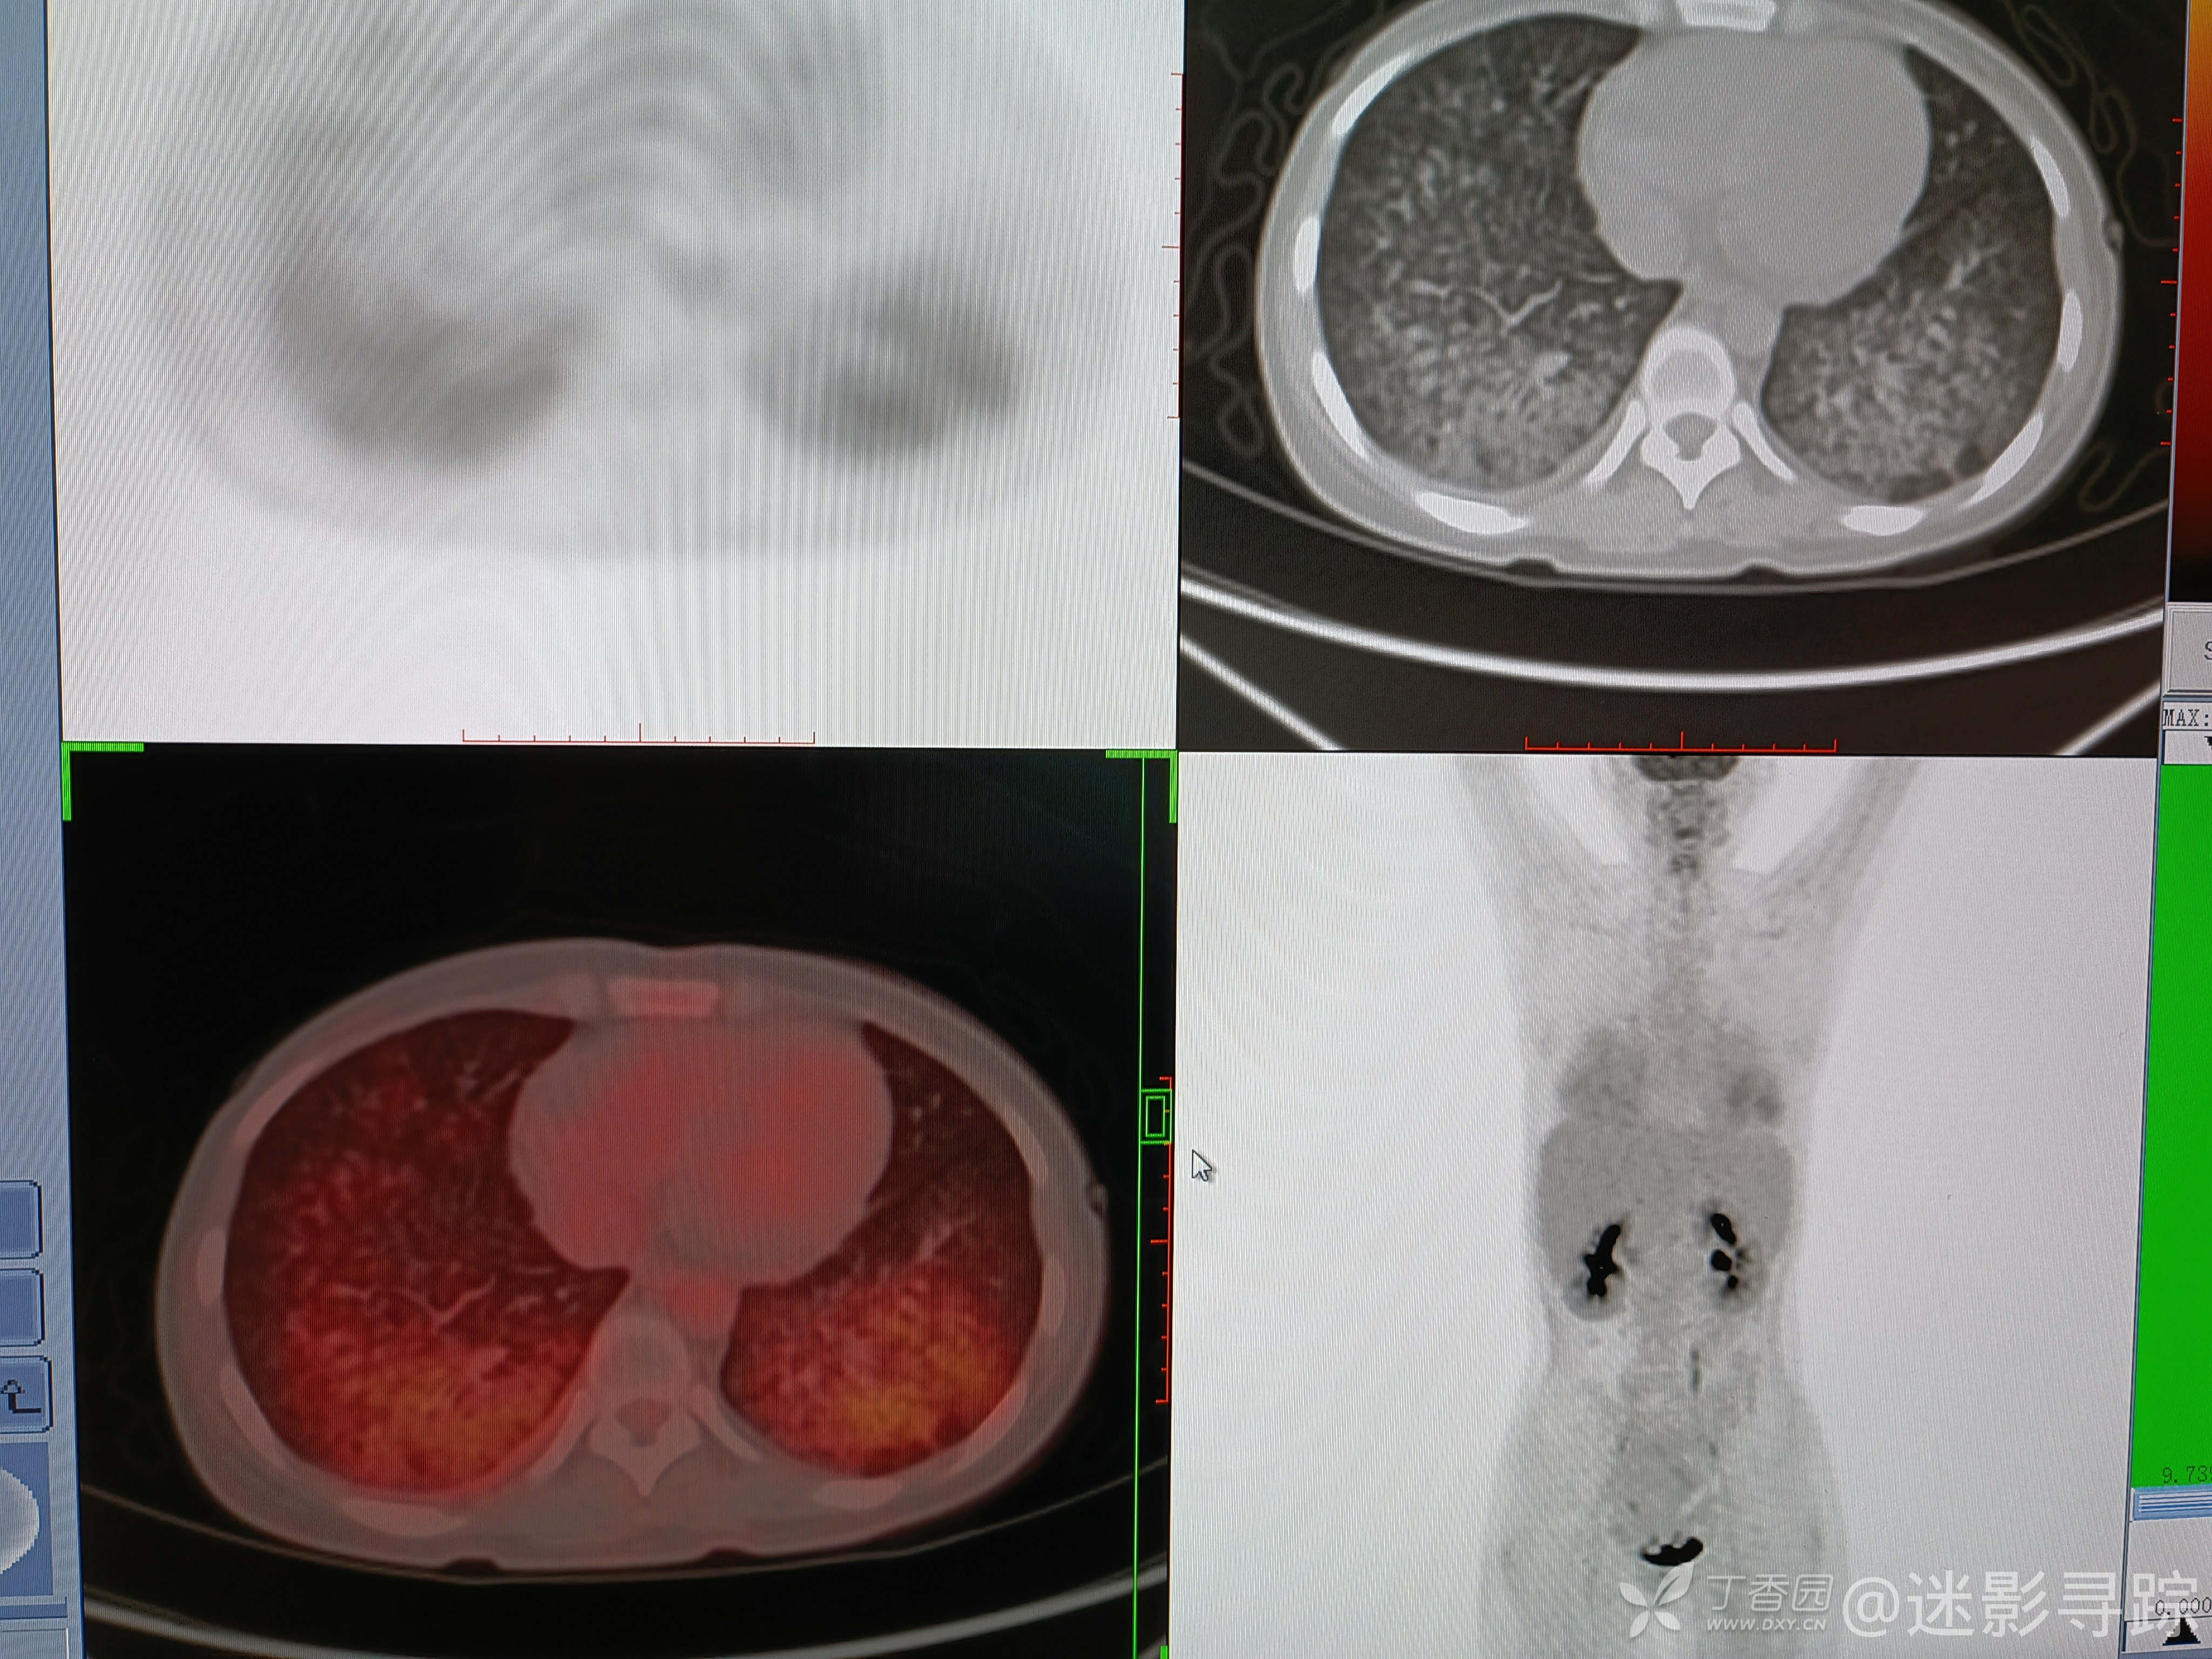

病例白血病髓外浸润化疗及移植后,双肺弥漫高密度影,考虑?补充PETCT,已公布结果!

女性,26岁,确诊白血病1年余,后发现髓外浸润,化疗后明显好转,后移植治疗。现因发热1周就诊。